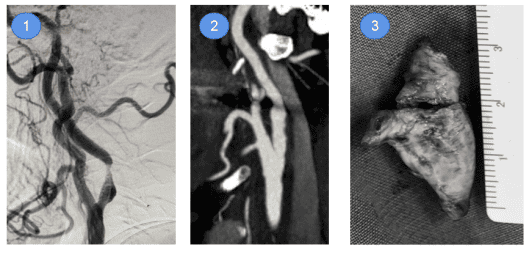

颈动脉内膜斑块导致颈动脉狭窄,是脑梗塞常见原因,本中心采用显微镜下切除斑块,比传统不用显微镜的手术方式,创伤更小,剥离更加精致干净,并发症更少。颈内动脉高度狭窄,术后颈内动脉狭窄消失,从血管内取下的斑块。